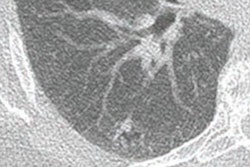

Tallam and colleagues conducted a study that included 8,992 patients who underwent colorectal cancer screening with CT colonography; of these, 572 had type 2 diabetes and 1,880 were dysglycemic. The researchers segmented images of the pancreas using a deep-learning algorithm that flagged biomarkers such as CT attenuation, volume, fat content, and the fractal dimension of the organ, as well as visceral fat and atherosclerotic plaque.

The deep-learning model showed that diabetics had lower pancreas CT attenuation and higher visceral fat than those patients who did not have the disease. Other key predictors of type 2 diabetes on CT included the following: